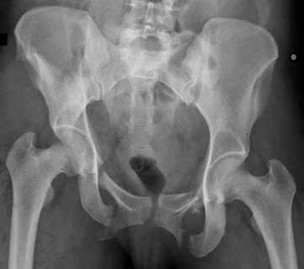

Figures 20a and 20b are the radiographs of a 19-year-old woman who was involved in a motor vehicle accident. What mechanism of injury is most consistent with the injury?